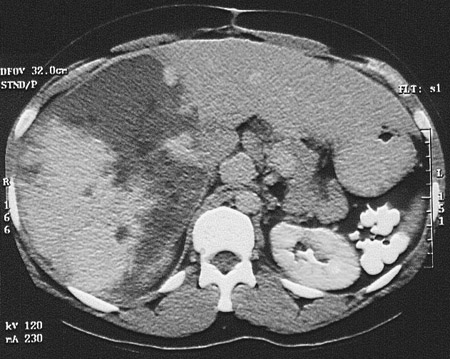

This computed tomographic (CT) scan of the abdomen reveals a very large mass lesion of the liver that varies in density. This is a giant cavernous hemangioma, a rare condition that can be symptomatic and require resection.